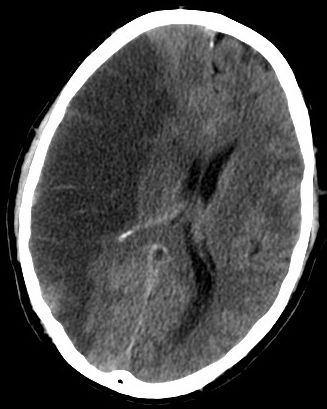

Felç sonrasında hastalar sıklıkla hafıza sorunlarıyla mücadele eder, bu sorunlar günlük yaşamda güçlükler yaratır. Hafıza problemlerinin şiddet ve türü, mod değişimleri ve günlük yaşam aktivitelerinde performans; felcin beyindeki yeri, şiddeti, yaş ve kişinin önceki sağlık durumu gibi birçok faktöre bağlı olarak değişir.